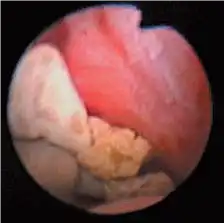

275°向下角度可在下部花萼中实现优良可视化。

通过在URF-P5内窥镜中加入莫尔减少滤波器,奥林巴斯成功地进一步提高了其光学数字成像性能。莫尔条纹减少效果为用户提供了高清晰的画面。